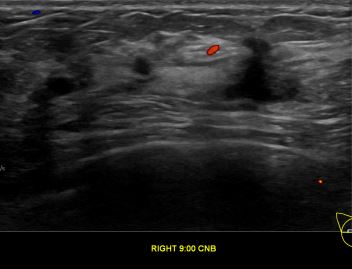

상기환자는 외부검사 이상소견으로 내원하신 40대중반 여성분으로 의심스러운 우측혹

조직검사 시행해 유방암으로 진단되었습니다